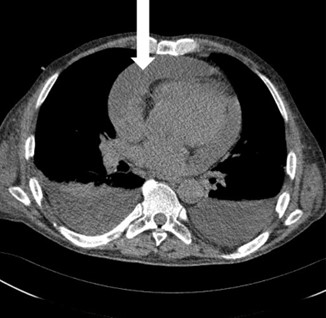

Valuable information on the character of the pericardial fluid is pded by the chest computed tomography (CT) image with the assessment of the attenuation value of the fluid (Hounsfield units–HU). Values between 20–60 HU suggest a purulent aetiology [8] (Fig. 3).

Fig. 3.

Fig. 3.Chest CT scan. White arrow a large amount of fluid in the pericardium.